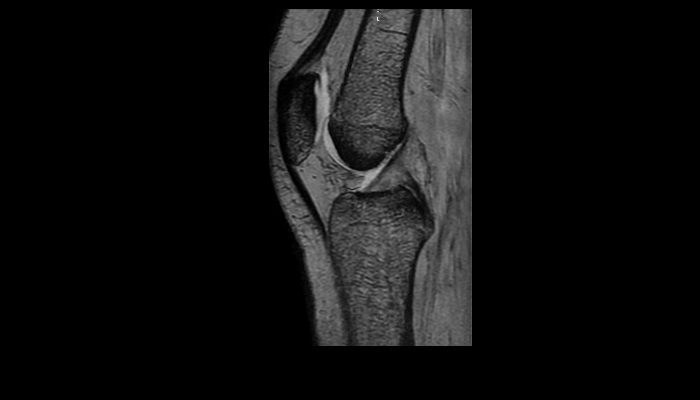

頭部MRI画像 頭部MRI脳腫瘍や脳梗塞、認知症など脳の病気を詳細に評価します。 MRA画像 頭部MRA造影剤を使わずに脳の動脈を描出します。動脈瘤や狭窄を検索します。 脊椎MRI画像 脊椎MRI椎間板ヘルニアや脊柱管狭窄症など脊椎や脊髄の疾患を評価します。 腹部MRI画像 上腹部MRI・MRCP肝臓・胆のう・膵臓・腎臓などの上腹部の重要臓器を詳細に評価します。 乳房MRI画像 乳腺MRIマンモグラフィや超音波と併せて、乳がんを検索や病変の範囲を評価します。 前立腺MRI画像 前立腺MRI前立腺がんを検索します。PSA高値の方はまず前立腺MRIをお勧めします。 子宮・卵巣MRI画像 子宮・卵巣子宮筋腫や子宮体癌、卵巣腫瘍など女性特有の病気を評価します。 膝関節MRI画像 膝関節膝関節の骨や靭帯、半月板を評価します。靭帯断裂や半月板損傷などレントゲンでは評価できない構造も診断できます。 肩関節MRI画像 肩関節肩関節の骨や腱、靭帯を評価します。腱板断裂や腱の断裂などレントゲンでは評価できない構造も診断できます。 心臓MRA 心臓MRA狭心症、心筋梗塞の原因となる冠動脈の狭窄を評価します。造影剤を使用せず、撮影可能です。 DWIBS画像 DWIBS全身のがんを広く検索します。リンパ節や転移の評価にも優れます。